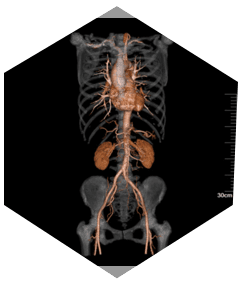

» Leistungsstarker CTA

» Bessere CTA-Qualitä

Großer Durchmesser für vielfältige Anwendungen

» 76 cm Scanbereich/

250 kg Tischkapazität und 21 Lp/cm Auflösung sind problemlos möglich

» Bequeme Positionierung von adipösen Patienten ohne

Kompromisse bei Dosis oder Bildqualität.